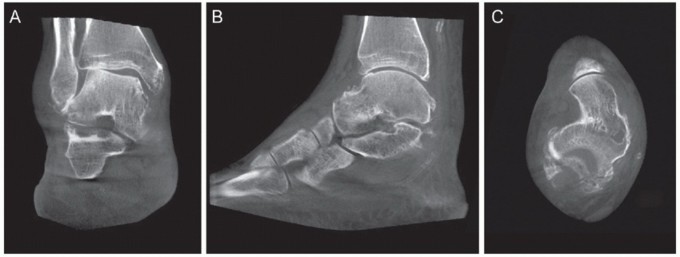

A computed tomography (CT) scan may be obtained to detect a talocalcaneal coalition or bony fragmentation that involves the articular surfaces. A weight-bearing CT may be beneficial to recognize the specific position of talus within the ankle mortise and a potential incongruency in the subtalar joint, as given by an accompanying peritalar instability (FIG 3).

55 FIG 3 • Weight-bearing CT in a patient with severe instability (same patient in FIG 2C). A. AP coronal plane.

B. Sagittal plane. C. AP horizontal plane.*